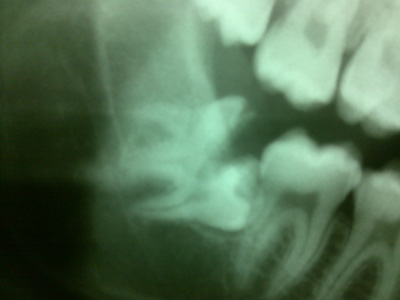

Estrazione del dente del giudizio 48 incluso in rapporto diretto con il Nervo Alveolare Inferiore destro

( Intervento e foto eseguiti da me in 20 minuti )